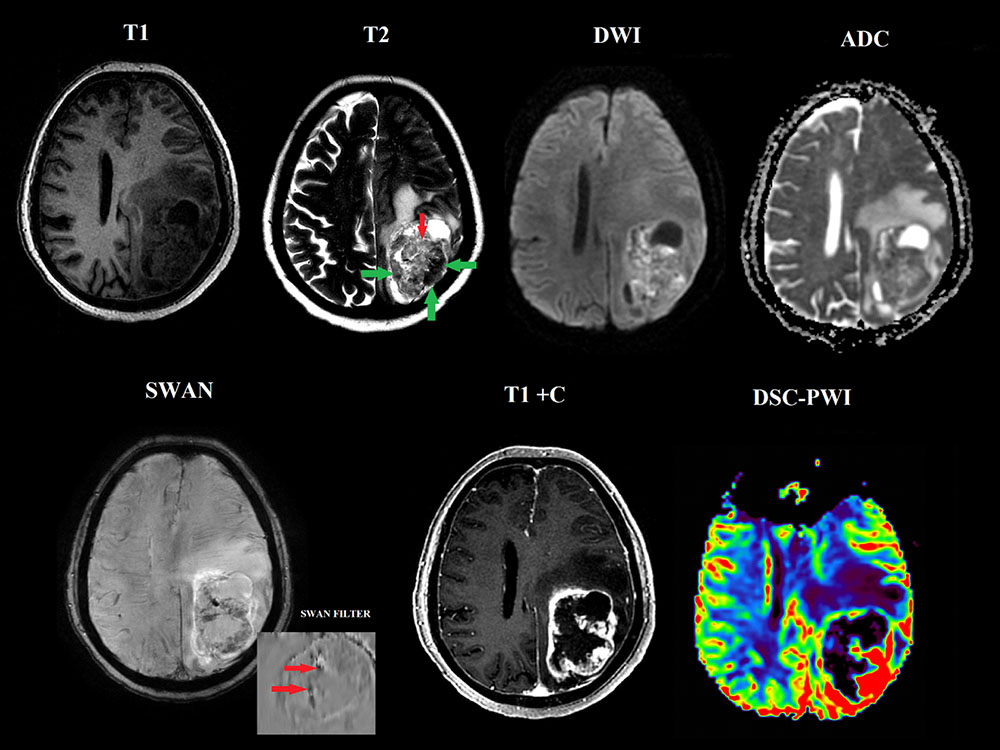

МРТ исследования головного мозга и DSC-перфузия. В левой теменной области интрааксиальное кистозно-солидное образование, с близким прилежанием к ТМО, окруженное выраженной зоной перифокального отека и масс-эффектом. При анализе Т2 последовательности, данная опухоль характеризуется наличием двухкомпонентной структуры, гипоинтенсивной более плотной (зеленые стрелки) и гиперинтенсивной (красная стрелка) клеточной. Отмечается выраженное и гетерогенное накопление парамагнетика опухолью на постконтрастных изображениях, а так же наличия диспластически расширенных сосудов с кровоизлияниями в структуре данной массы на последовательностях SWAN. На перфузионных картах образование демонстрирует высокие значения относительного мозгового кровотока опухоли (превышающие нормальные значения в 7-8 раз).